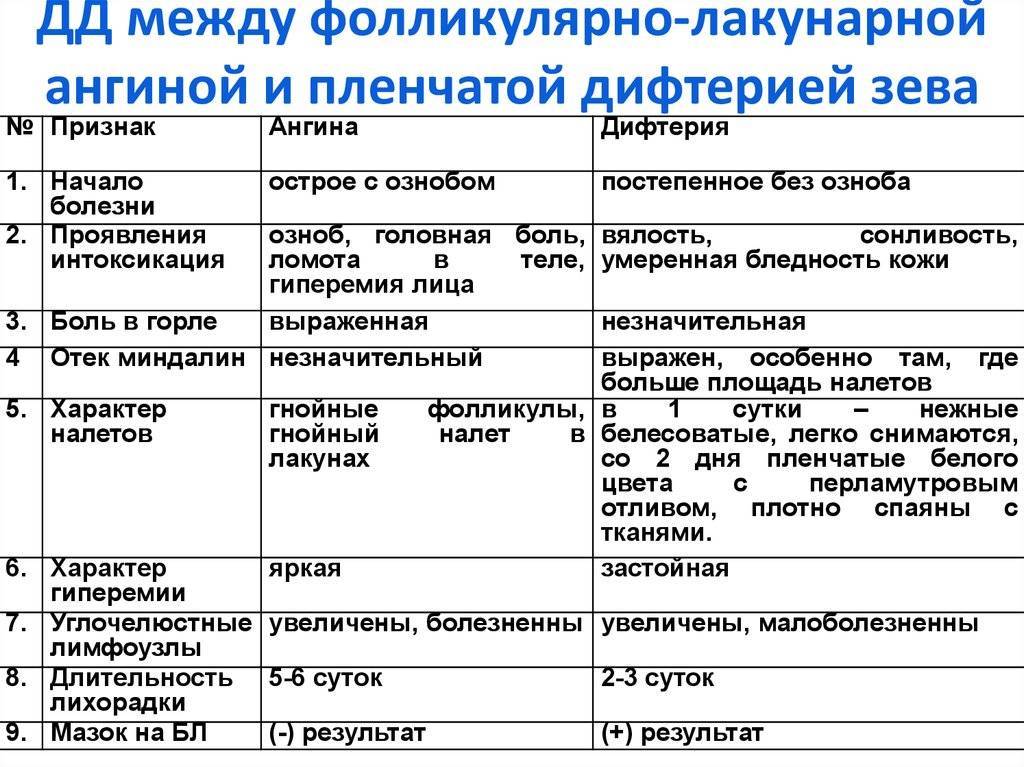

Клиническое течение при ангине у каждого ребенка может отличаться, учитывая тип заболевания:

- Катаральная, которая является наиболее распространенной и протекает легче, чем другие типы болезни. Проявляется поверхностным поражением миндалин с появлением небольших красных участков на слизистой оболочке. Симптоматика выражена не остро, при этом возможно незначительное повышение температуры до 37-38°С. Ребенку часто ставится такой диагноз при развитии заболеваний верхних дыхательных путей.

- Фолликулярная или гнойная. Отличается более острым течением, часто сопровождается высокой температурой – 38°С и выше. При подобной форме на миндалинах можно обнаружить небольшие белые или желтые гнойники не больше 2 мм. При гнойной ангине увеличиваются и болят при пальпации лимфоузлы на шее и затылочной части.

- Лакунарная. Характерным признаком является ярко выраженная клиническая картина, при этом гнойные образования локализуются на протоках небных миндалин (лакунах).

Если организм ослаблен, бактерии могут проникнуть в миндалины и начать размножаться, вызывая патологические изменения в лимфоидной ткани. Это приводит к развитию катарального воспаления, которое может прогрессировать в гнойный процесс. В результате возникает фолликулярная ангина, которая характеризуется наличием гнойных изменений в фолликулах. При осмотре зева видна “звездная” картина, где на гиперемированном фоне можно увидеть точечные скопления гноя белого или беловато-желтого цвета. Процесс продолжается, гнойные фолликулы вскрываются, гной вытекает и проникает в лакуны, где образуется новый очаг воспаления, что приводит к лакунарной ангине.

Разделение на фолликулярную и лакунарную формы условное, поскольку часто обе стадии диагностируются одновременно. По клиническому течению они практически не отличаются, разница заключается только в фарингоскопической картине. При осмотре зева видны лакуны, заполненные гноем, которые имеют неправильную форму и напоминают поверхность “гриба мухомора”

Классификация ангины

По степени воспаленности миндалин, ангина у детей может иметь несколько видов:

- катаральная. При осмотре зева видно, что небные дужки, миндалины увеличены и покрыты серозным белесоватым налетом;

- фолликулярная. Характерным признаком является наличие гнойных точек на миндалинах, размер которых может быть до трех миллиметров;

- лакунарная. Осмотр зева, открывает отекшие и сильно покрасневшие миндалины, покрытые налетом гноя, желтого цвета;